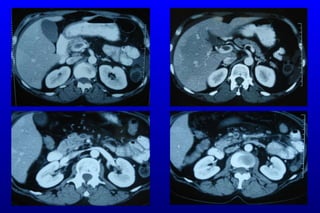

Tanı Önceki yıllar:  klinik tanı, konvansiyonel anjiografi ,  DPL Günümüzde:  BT anjiografi,  Sensitivit e :  %  96 Multidetektör - multislice  Spe s i f i te : %   94 Avantajlar Vasküler anatomi Ayırt edici tan ı

BT Anjiografi: Multidete k t ö r  BT akut ve kronik mezenterik iskeminin tanısında idealdir   Horton KM, et al.  Radiol Clin North Am. 2007 Mar;45(2):275-88. Review

CTA: SMA Emboli

SMV Trombozu